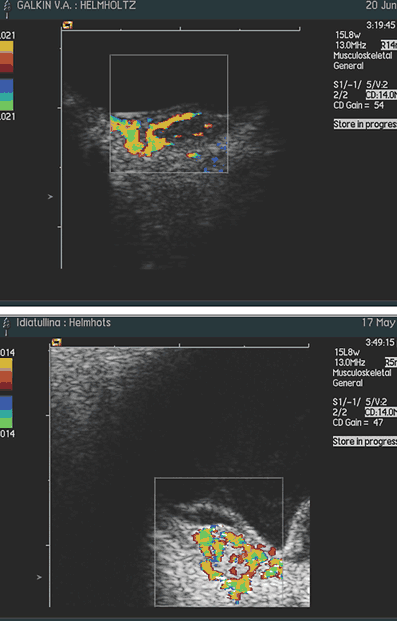

При исследовании в режиме ЦДК во всех случаях, независимо от размеров отграниченной гемангиомы, выявлено равномерное распределение новообразованных сосудов по всей ее толщине и площади. Визуально кровоснабжение гемангиомы осуществляется за счет сосудов хориоидеи: сосуды сетчатки не участвуют в ее питании (рис. 3, 4) Только при юкстапапиллярной локализации (3 случая) опухоль получала двойное кровоснабжение – за счет сосудов хориоидеи и ЦАС (рис. 5).

Рис. 3, 4: Цветовое допплеровское картирование гемангиомы макулярной локализации